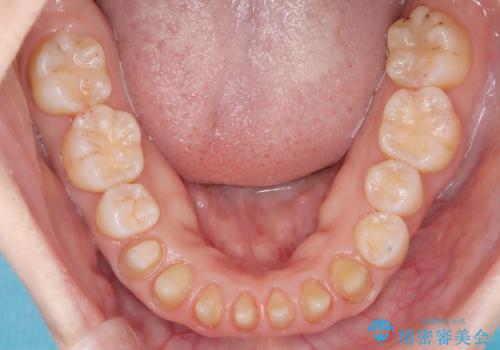

【オールセラミック】下の前歯が痛い。

- 以前に治療した前歯が痛むことを主訴に来院されました。

根っこに病気があり、根管治療から被せ物まで治療を行いました。

根管治療を行った後、3ヶ月間治癒の確認をしてからオールセラミックスペシャルで治療を行いました。